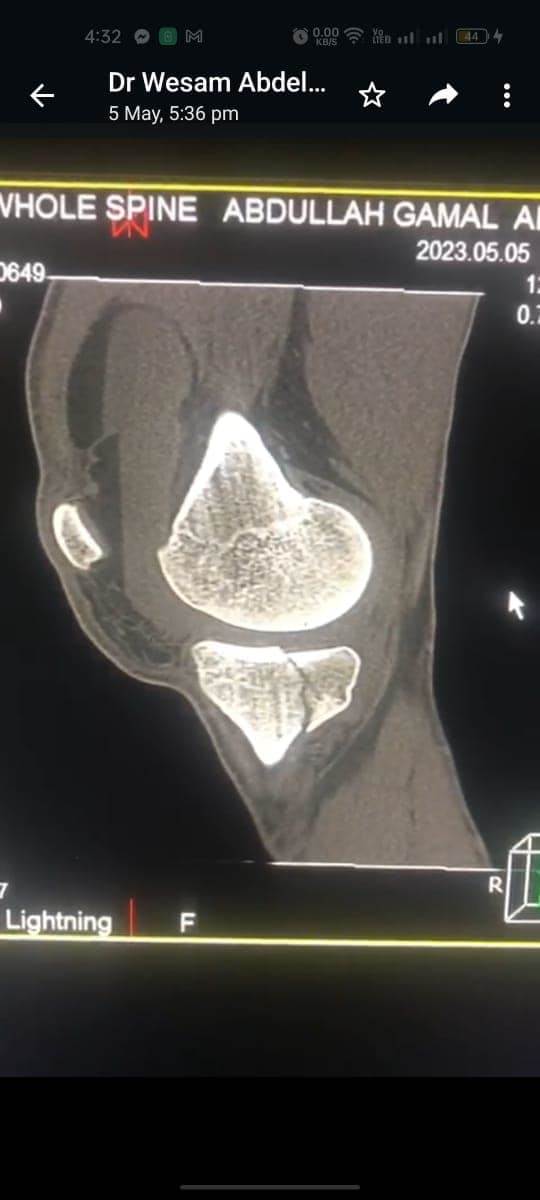

مشيرًا الى أن ذلك النوع من الكسور يكون قريبًا جدًا من الأعصاب والأوعية الدموية الرئيسية للساق والتي توجد خلف مفصل الركبة.. حيث تم الوصول الى الكسر وإعادة بناء سطح المفصل وتثبيته باستخدام شريحة ومسامير وأسلاك معدنية باستخدام جرح ٧ سنتيمترات خلف الركبة واستخدام مسامير جانبية مجوفة بدون فتح لتثبيت الجزء الخارجى من سطح المفصل، وتم الاطمئنان على الأوعية الدموية قبل إفاقة المريض، وبعد تمام الإفاقة.. تم الاطمئنان على الأعصاب والأوعية للمريض.

وأضاف أنه نظرًا لقرب هذا الكسر من سطح المفصل تم عمل أشعة مقطعية بعد الجراحة للتأكد من جودة بناء المفصل وعدم وجود أى بروز للمسامير داخل المفصل، وجارٍ تحضير المريض لعمل رنين مغناطيسى لتحديد الأربطة الداخلية والخارجية للركبة التي ستحتاج لإعادة بناء بالمنظار.